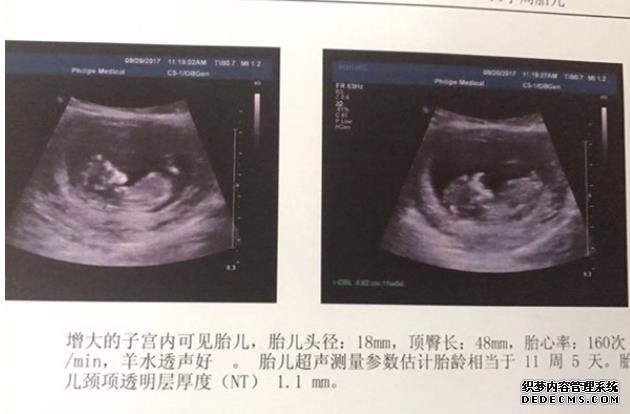

今天是移植的第17天,孕酮60,hcg1853,希望宝宝好好健康成长,希望各位姐妹们早日圆母亲梦!